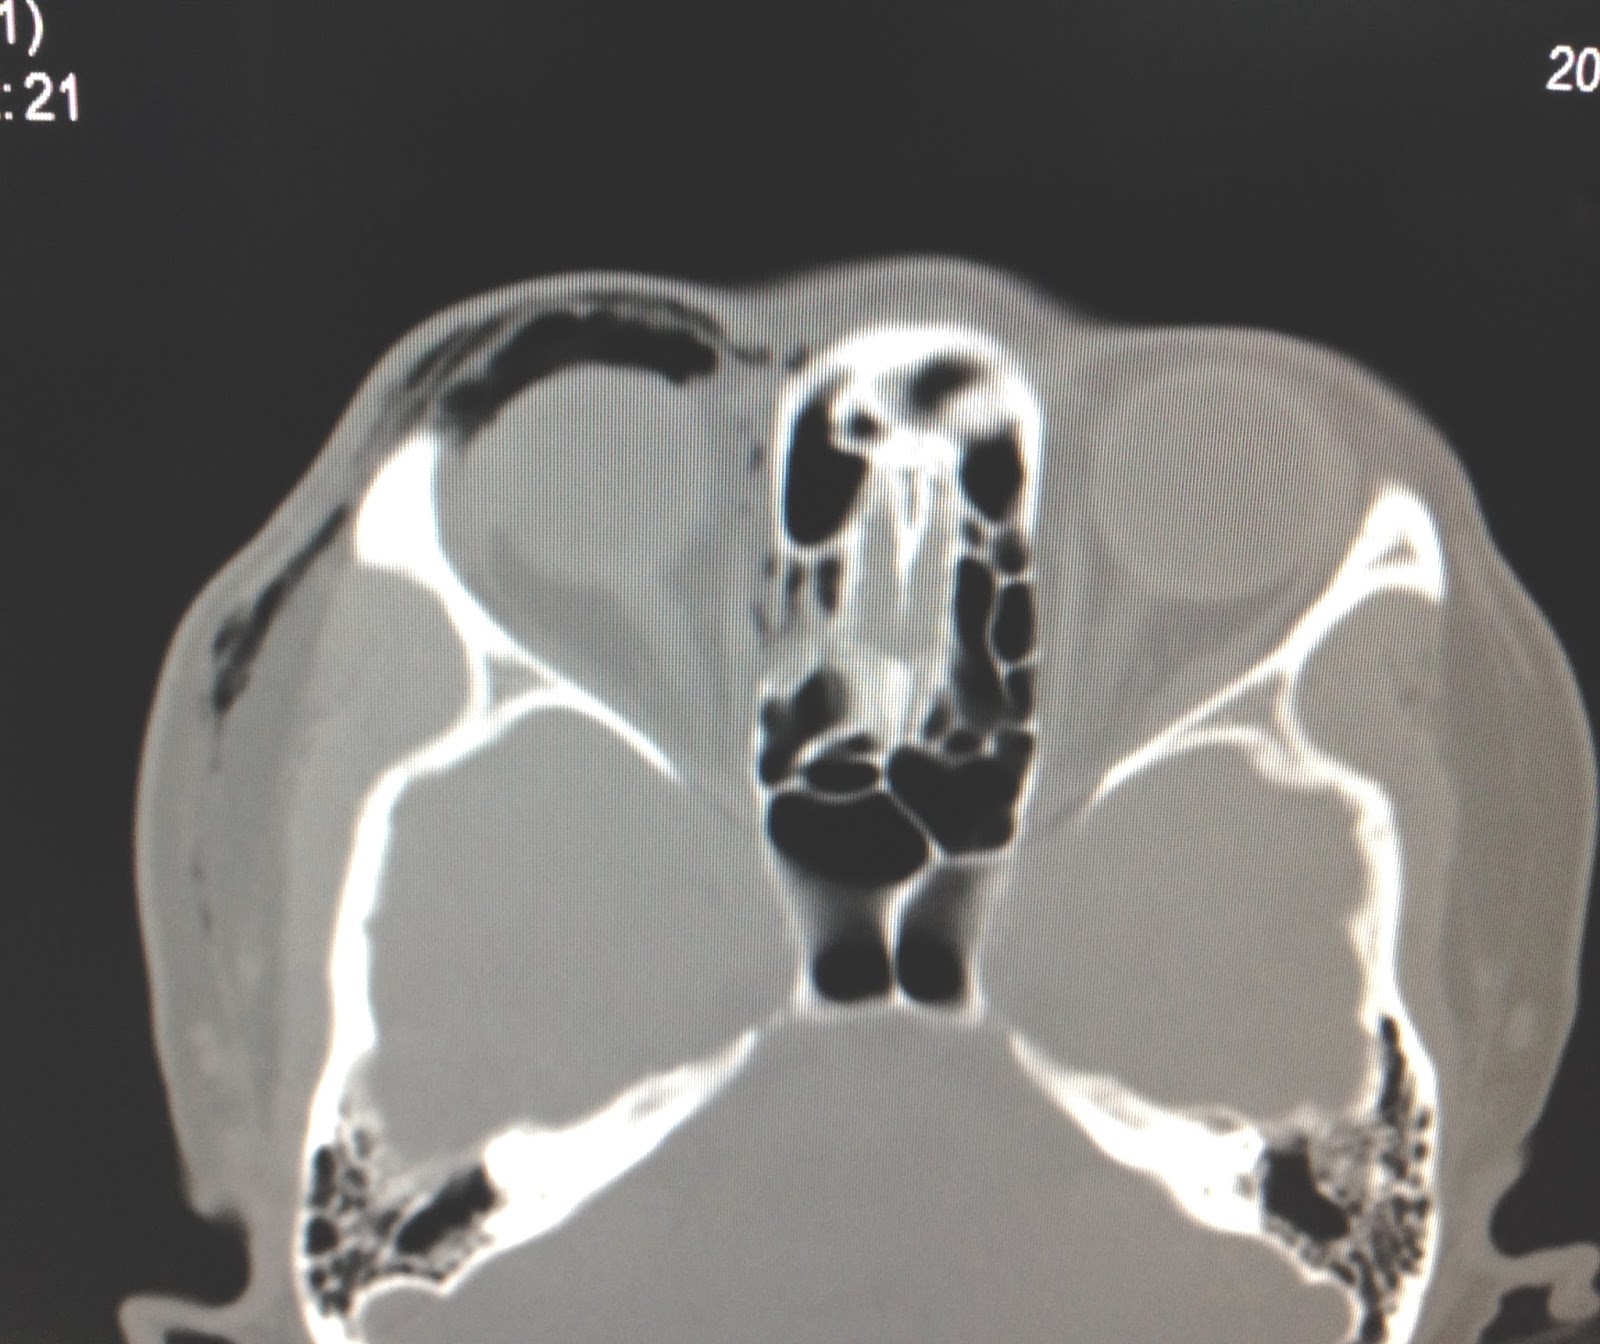

VIETNAMESE MEDIC ULTRASOUND CASE 423 BLACK EYEBROW SIGN, Dr PHAN

Eyebrow X Ray Sign . This is visible as a dark patch. Learn how to assess facial bones on radiographs using systematic approach, common lines and projections. The black eyebrow sign indicates orbital emphysema, typically from a orbital fracture, with air having entered from the adjacent sinuses. The black eyebrow sign is the description given to air in the superior part of the orbit, almost exclusively occuring in the context of an orbital. Air rises into the most. Learn how to interpret the occipitomental (om) view of the face, which shows the frontal sinuses, orbits, maxillary. Associated fracture of the maxillary sinus allows air to leak into the orbit.

Air rises into the most. The black eyebrow sign is the description given to air in the superior part of the orbit, almost exclusively occuring in the context of an orbital. Learn how to assess facial bones on radiographs using systematic approach, common lines and projections. The black eyebrow sign indicates orbital emphysema, typically from a orbital fracture, with air having entered from the adjacent sinuses. Learn how to interpret the occipitomental (om) view of the face, which shows the frontal sinuses, orbits, maxillary. This is visible as a dark patch. Associated fracture of the maxillary sinus allows air to leak into the orbit.